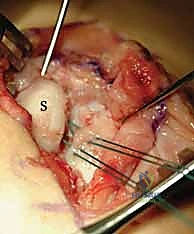

We meticulously debride the interposed hematoma, synovitis, and any frayed, non-viable ligamentous edges using a small rongeur and a motorized shaver. Typically, the dorsal SLIL avulses from its scaphoid footprint, leaving a robust stump attached to the lunate.

This high-magnification view clearly demonstrates the scaphoid on the left and the viable SLIL stump remaining attached to the lunate on the right, grasped securely by forceps.